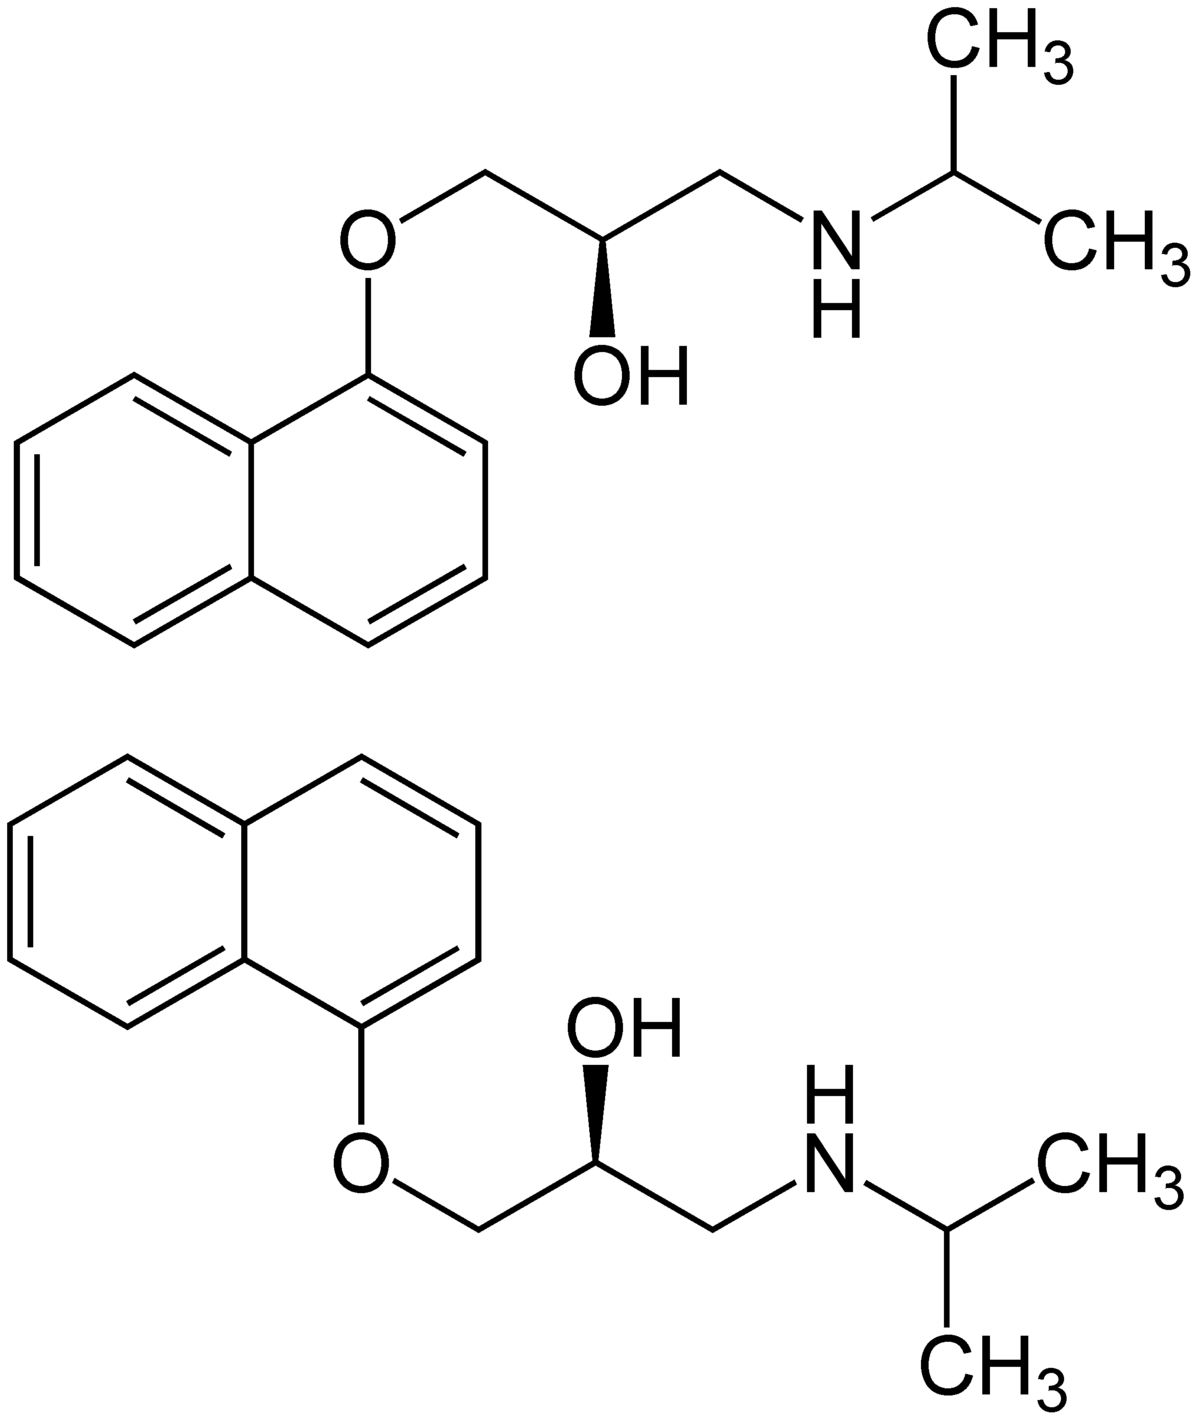

Es posible que los β-bloqueadores actúen, al menos parcialmente, mediante alguna acción central en el centros de control cardiovascular del cerebro. Los betabloqueantes también bloquean los receptores de los vasos sanguíneos periféricos, los riñones y los bronquios. Los principales efectos de esto son la vasoconstricción en los músculos esqueléticos que causan frío en las extremidades. y secreción reducida de renina, que limitaría la formación de angiotensina II. betabloqueantes puede precipitar el asma y no debe usarse propranolol 10 mg capsulas personas con asma.

Los betabloqueantes se utilizan para tratar la cardiopatía isquémica, la arritmia y la hipertensión. Estos fármacos ejercen su efecto en la angina inducida por el ejercicio al reducir el aumento de frecuencia cardíaca y fuerza de contracción en respuesta al ejercicio, reduciendo así el oxígeno demanda del miocardio. Los betabloqueantes se pueden utilizar de forma profiláctica en el tratamiento. de angina estable.